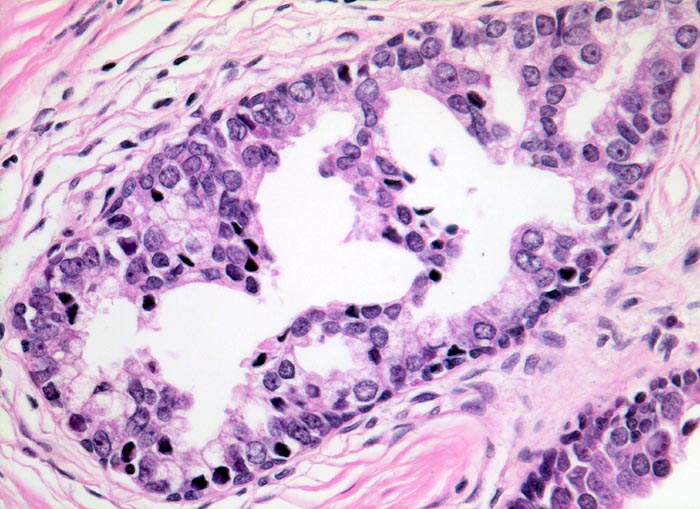

prostatische intraepitheliale Neoplasie (high grade PIN)

Grösserer Drüsenschlauch mit komplexen mikropapillären und kribriformen Epithelproliferationen. Die Epithelzellen haben vergrösserte atypische Kerne mit deutlich erkennbaren Nukleolen. Eine Basalzellschicht ist erkennbar.

Prostatische intraepitheliale Neoplasien sind gekennzeichnet durch grössere Drüsen mit deutlichen Zellatypien. Im Gegensatz zum Adenokarzinom lassen sich aber Basalzellen nachweisen. High grade PIN sind in der Umgebung fortgeschrittener Karzinome fast immer nachweisbar. Wenn in einer Prostatabiopsie lediglich high grade PIN, aber kein Karzinom nachweisbar ist, sollte rebiopsiert werden. Denn beim Vorliegen eines high grade PIN liegt in etwa 50% an anderer Stelle ein invasives Adenokarzinom vor.